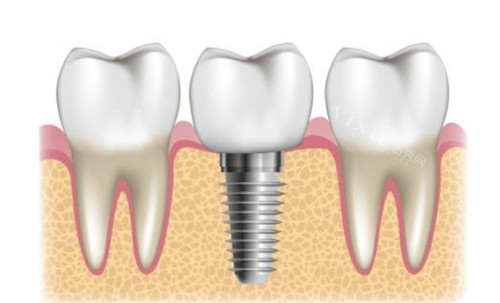

绍兴越城麦芽口腔种植牙价格表

国产种植牙:680 元起

韩国登腾(Dentium)种植牙:2800 元起

韩国奥齿泰(Osstem)种植牙:4200 元起

瑞士 ITI 种植牙(Straumann):7000 元起

德国 ICX 种植牙:6500 元起

美国皓圣(HIOSSEN)种植牙:4800 元起

以色列种植牙:5169 元起

瑞士 SIC 种植牙:5580 元起

瑞典诺贝尔种植牙:7800 元起

半口种植牙:50000 元起